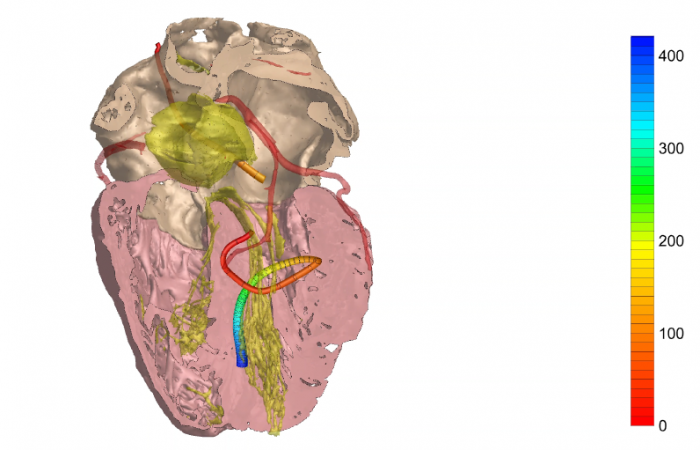

Pracownia Funkcjonalnego i Wirtualnego Medycznego Obrazowania 3D

(ang. Laboratory of Functional and Virtual Medical 3D Imaging, akronim: 3D-vFMi(maging), skrót: 3D-FM)

Pracownia Funkcjonalnego i Wirtualnego Medycznego Obrazowania 3D (Pracownia 3D-FM) funkcjonuje w strukturze Zakładu Diagnostyki Obrazowej Szpitala Uniwersyteckiego w Krakowie pod kierownictwem Prof. dr hab. Tadeusza Popieli. Jej celem jest opracowanie i wdrożenie innowacyjnych metod przetwarzania oraz analizy sygnałów i obrazów medycznych, w tym wykorzystanie technologii rzeczywistości wirtualnej oraz metod obrazowania funkcjonalnego. Rozwiązania te wspierają przedoperacyjne planowanie, monitorowanie procedur medycznych oraz wzbogacają proces diagnostyczny o nowe formy wizualizacji danych medycznych.

Pracownia 3D-FM zajmuje się m.in. następującymi obszarami:

- Tworzeniem modeli 3D do celów przedoperacyjnego planowania oraz wizualizacji diagnostycznej.

- Obrazowanie Medyczne 3D

- Segmentacja i analiza danych DICOM

- Rekonstrukcja danych medycznych

- Elektrokardiograficzne obrazowanie 3D (ECGI)

- Modelowanie fizjologiczne